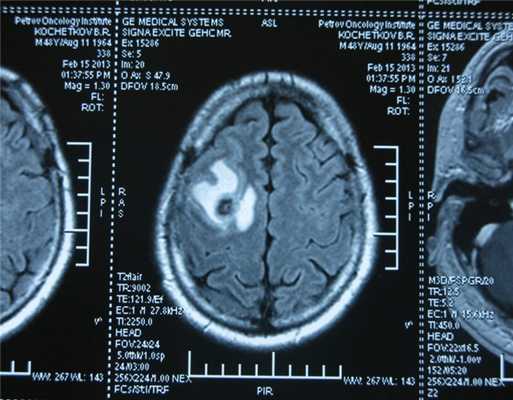

Рисунок 7. - Герминома головного мозга.

Рисунок 9. - метастаз в головной мозг при герминогенной опухоли.

Также выполняют МРТ головного мозга, чтобы выявить наличие метастазов в нем.

![Метастаз в головной мозг при герминогенных опухолях (МРТ головного мозга)]()

Метастаз в головной мозг при герминогенных опухолях (МРТ головного мозга)